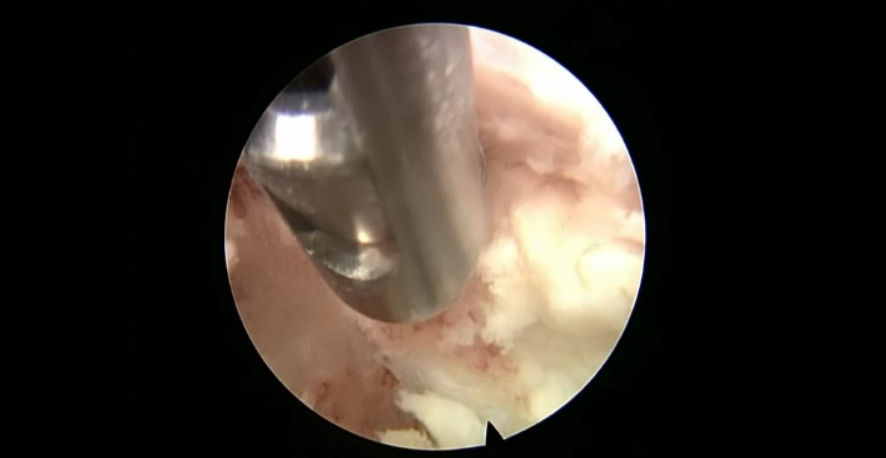

术中资料

点击以上图片,查看术中视频(超链接:http://res.orthonline.com.cn/video/case5---20.mp4)

点击以上图片,查看术中视频(超链接:http://res.orthonline.com.cn/video/case5---30.mp4)